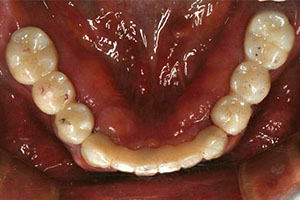

치료증례 전후사진

Before & After